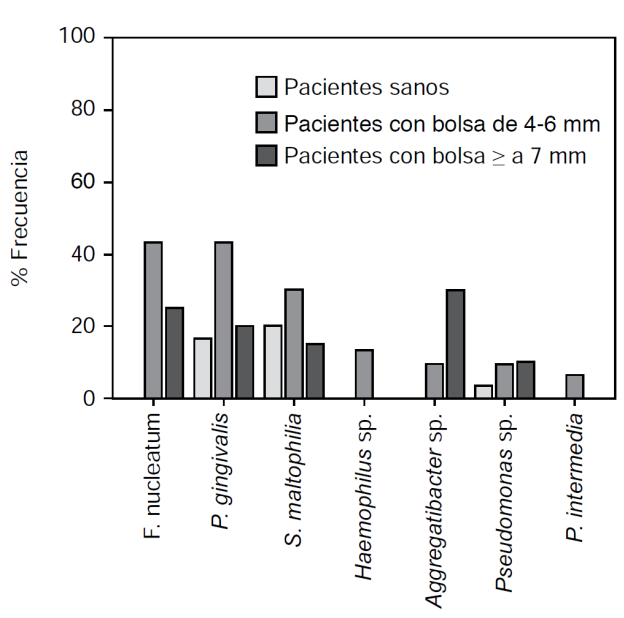

Las bacterias detectadas en este estudio fueron: Stenotrophomonas maltophilia, Porphyromonas gingivalis, Pseudomonas sp., Fusobacterium nucleatum, Haemophilus sp., Aggregatibacter sp. y Prevotella intermedia, las cuales tuvieron una distribución diferente entre los grupos de estudio (Cuadro I y Figura 3), encontrando asociación entre la presencia de P. gingivalis y el grupo de periodontitis moderada (OR = 3.8, IC = 1.2-12.7, p = 0.02) y periodontitis severa (OR = 11.6, IC = 3.0-45.2, p < 0.001). Igualmente, se asoció la presencia de F. nucleatum con periodontitis moderada y (OR = 47.1, IC = 2.6-841, p = 0.008) y periodontitis severa (OR = 21.6, IC 1.1-417, p = 0.04). Asimismo, se asoció la presencia de Aggregatibacter sp. con periodontitis severa (OR = 27.3, IC 1.4-519, p = 0.02).

Cuadro I Frecuencia y distribución de las bacterias en los grupos de estudio.

| Bacteria | Sanos n = 30 (%) | Periodontitis moderada n = 30 (%) | Periodontitis severa n = 20 (%) | p |

| Stenotrophomonas maltophilia | 6 (20) | 9 (30) | 3 (15) | 0.423 |

| Porphyromonas gingivalis | 5 (16.6) | 13 (43.3) | 4 (20) | 0.047* |

| Pseudomonas sp. | 1 (3.3) | 3 (10) | 2 (10) | 0.548 |

| Fusobacterium nucleatum | 0 | 13 (43.3) | 5 (25) | < 0.001* |

| Haemophilus sp. | 0 | 4 (13.3) | 0 | 0.03* |

| Aggregatibacter sp. | 0 | 3 (10) | 6 (30) | 0.004* |

| Prevotella intermedia | 0 | 2 (6.6) | 0 | 0.181 |

* Significancia estadística entre los grupos.

Los resultados en la identificación bacteriana en general mostraron bacterias reportadas por otros autores tanto en pacientes sanos como enfermos;6 sin embargo, la frecuencia de ellas y sus asociaciones fueron características en cada grupo de estudio, sugiriendo como está descrito en la patología que un desbalance de microorganismos puede conducir a enfermedad.4

Cabe destacar que en los tres grupos de estudio fue detectada P. gingivalis, una bacteria que conforma el denominado complejo rojo con Tannerella forsythia y Treponema denticola, el cual se ha asociado con periodontitisagresiva;3 sin embargo, la frecuencia de esta bacteria fue más alta en el grupo de pacientes con periodontitis moderada y su presencia se asoció con los dos grupos de periodontitis.

Curtis y Darveau, en 2011, mencionan que en pacientes sanos se ha encontrado a P. gingivalis, lo que indica que su presencia sola no es la responsable de la enfermedad,3 otros grupos han descrito que P. gingivalis puede interaccionar con Strepto-coccus gordonii, y favorecer la colonización de otros patógenos conduciendo a la enfermedad.14 En este estudio, se observó que P. gingivalis y F. nucleatum fueron detectadas con mayor frecuencia en pacientes con periodontitis moderada y se asociaron con los dos tipos de periodontitis. Esta evidencia sugiere que la asociación de estas bacterias podría estar favoreciendo la colonización de otros patógenos, tales como Aggregatibacter sp., la cual predominó y se asoció a periodontitis severa, como se ha documentado en otros reportes.15 En periodontitis severa también predominó y se asoció F. nucleatum, lo que también podría sugerir que la asociación entre Aggregatibacter sp. y F. nucleatum es idónea para sobrevivir y florecer en el periodonto y progresar a una periodontitis crónica destructiva en la que se da una desregulación del proceso inflamatorio que a su vez proporciona nuevos nutrientes para las bacterias, los cuales son derivados de la destrucción del tejido, como lo han reportado otros autores.9,16

Con respecto al resto de las bacterias detectadas aquí, se reporta la presencia en este padecimiento, pero no como el principal causante, sino como bacterias que manejan una simbiosis con otras, o bien como oportunistas de otras bacterias responsables de la periodontitis como es el caso de Stenotrophomonas maltophilia que se ha reportado incluso como oportunista en gingivitis en pacientes con leucemia.19 Respecto a Pseudomonas sp., Haemophilus sp. y Prevotella intermedia, se han encontrado también en cavidad bucal de pacientes sanos; sin embargo, su frecuencia es mayor en pacientes con periodontitis.20,21